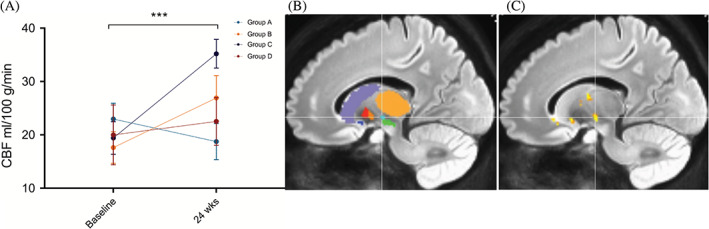

偽連續動脈旋轉顯示時間( P<0.001)和區域(P<0.001)的主效應顯著,但半球( P=0.401)或隊列(P=0.088)?的主效應不顯著。所有基底神經節結構的灌注從基線到輸注后24周總體增加。事后按區域時間比較顯示,同種異體hMSC輸注后,隨時間變化的灌注增加最顯著的是丘腦底核(圖2)。

圖2:灌注變化